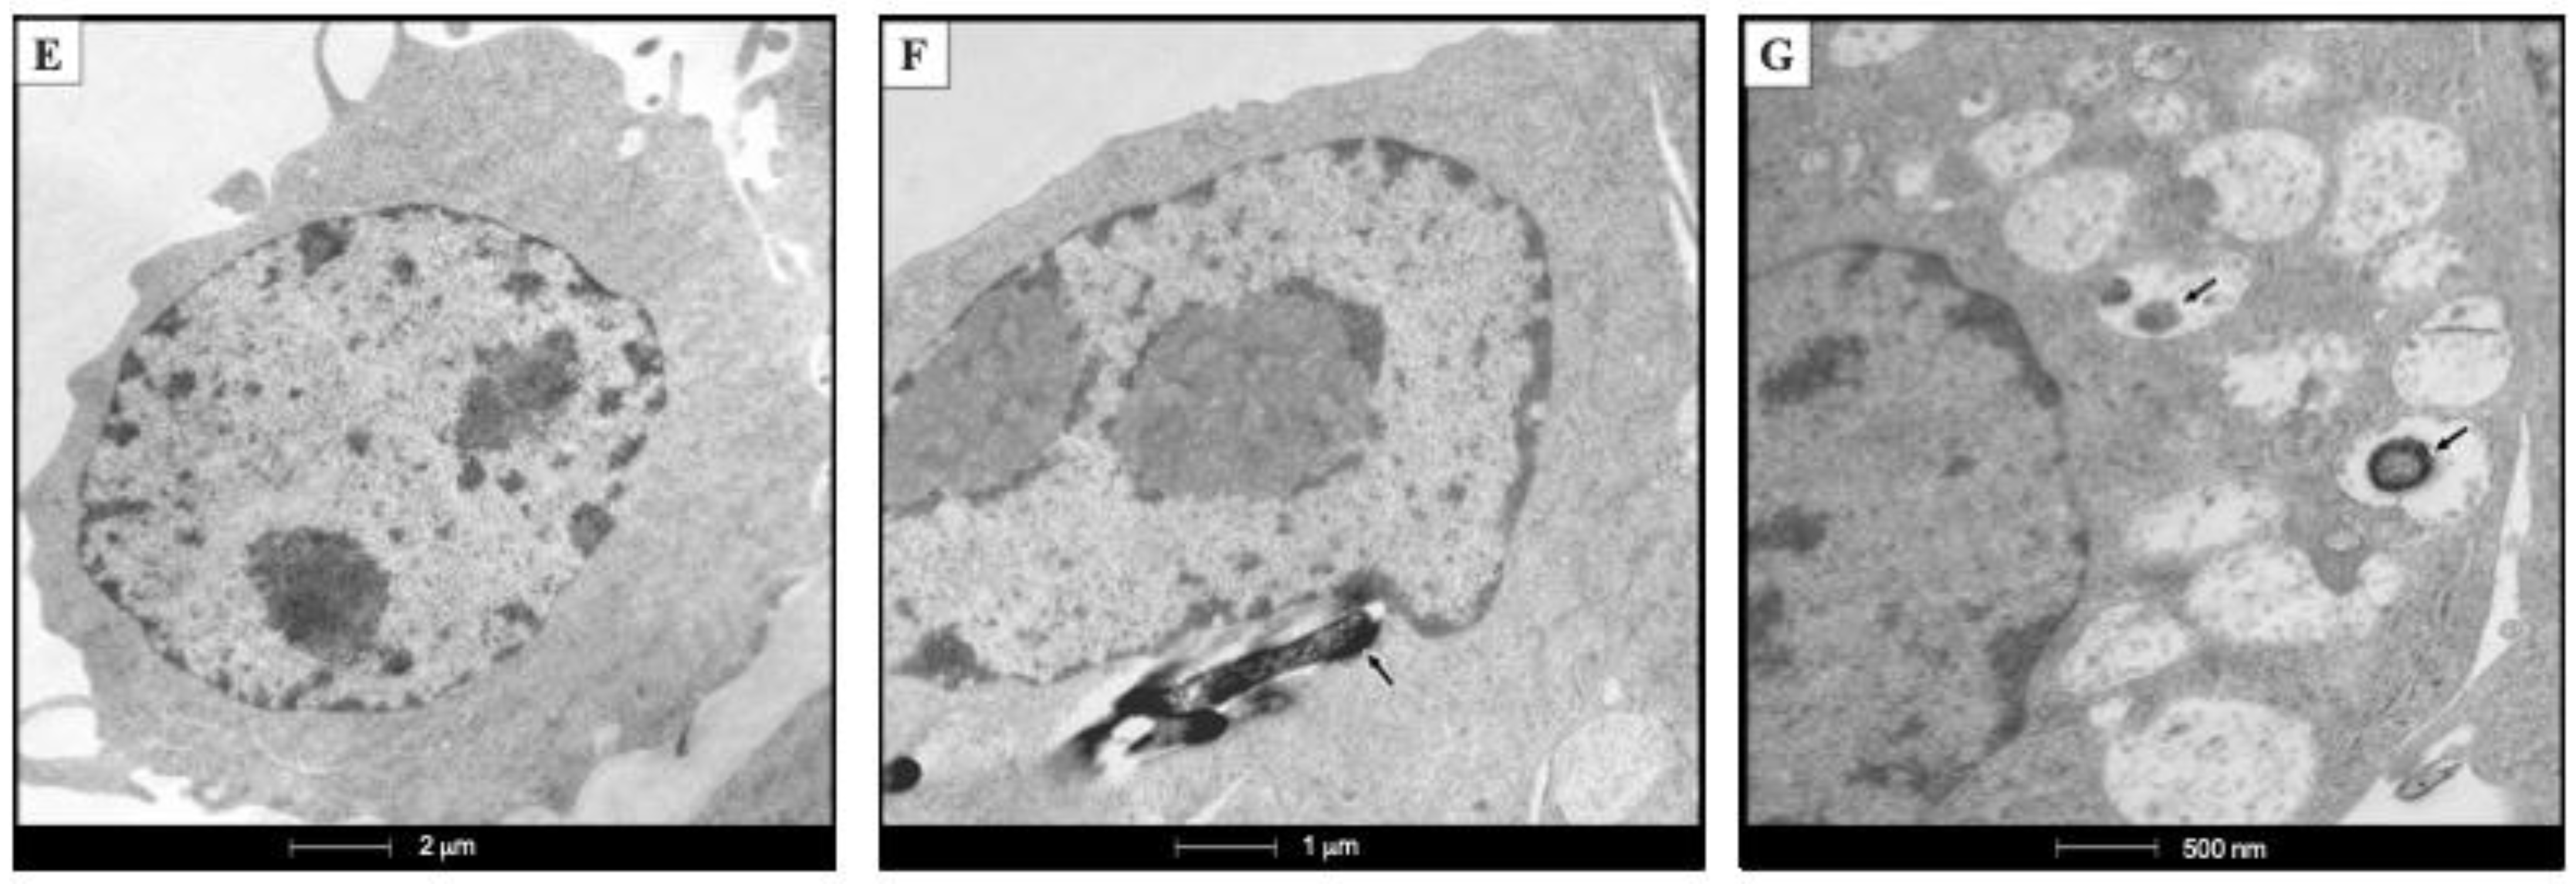

Representative ultrastructural micrographs of mycobacteria (upper row) and infected alveolar macrophages (lower row). (A) Typical morphology of MtbH37Rv strain. (B) High power micrograph of the cell envelope of MtbH37Rv shows three layers: an electron-dense outer layer (OL), electron transparent layer (ETL) and peptidoglycan layer (PGL). (C) Abnormal morphology of the Mtb∆ctpF strain, showing an irregular shape with projections and concavities on the bacterial surface. (D) High power micrograph of the cell envelope of Mtb∆ctpF showing thinner outer and peptidoglycan layers. (E) Normal ultrastructure of non-infected MH-S cells. (F) At 3 days post-infection (dpi) macrophages show a phagosome with electron-dense long rods that correspond to MtbH37Rv (arrow). (G) At 3 dpi with Mtb∆ctpF, macrophages show numerous vacuoles with granular electron-dense material or small bacteria (arrow).

To evaluate whether the ctpF gene is relevant for the intracellular growth of Mtb, an infection model of MH-S cells was used. Both parental and mutant strains showed similar levels of infection of MH-S cells at 1 h (the time at which mycobacteria are phagocytosed [49]), indicating that the ctpF deletion does not alter the initial ability of Mtb to infect phagocytic cells, such as MH-S cells (Figure 3A). However, when the infection process advanced, a significant decrease in replication of the mutant strain, relative to the parental strain, was observed, especially between 3 and 7 dpi (**** p < 0.0001) (Figure 3A). Indeed, the MtbH37Rv strain showed a 112-fold increase in the number of colony-forming units (CFU) during 7 dpi (1 h and 7 dpi: 5033 and 566,667 CFU/mL, respectively), while the mutant MtbΔctpF strain showed only a 6-fold increase (1 h and 7 dpi: 4880 and 27,333 CFU/mL, respectively). Moreover, our ultrastructural study of infected MHS cells showed more phagosomes, phagolysosomes and autophagosomes in macrophages infected with the mutant strain than in those infected with the parental strain (Figure 2E–G), which indicates that the Mtb∆ctpF strain was eliminated more easily. These results suggest that CtpF is required for the survival and optimal intracellular multiplication of Mtb in MH-S macrophages (Figure 2 and Figure 3).